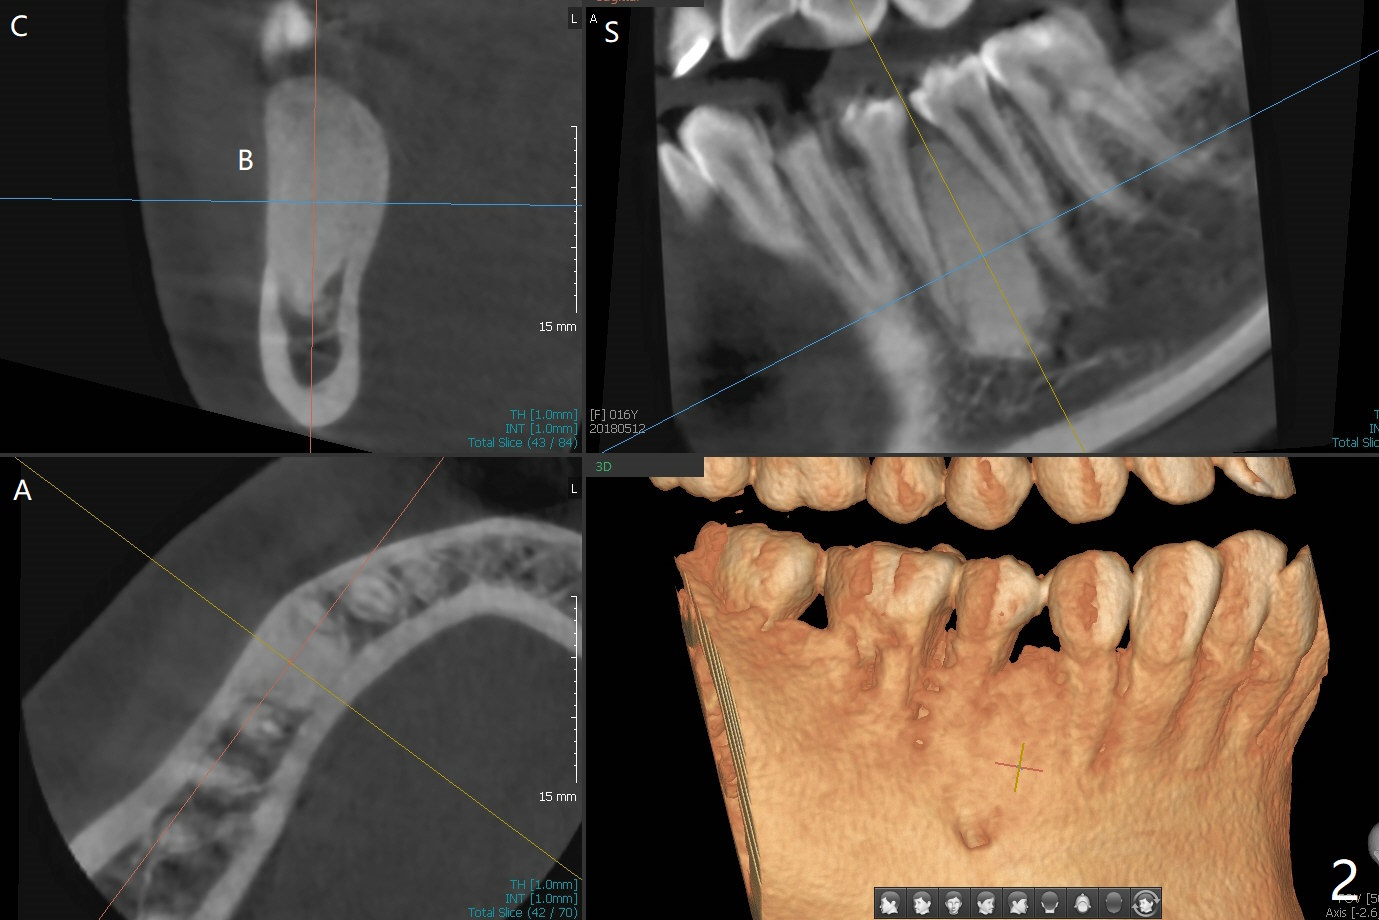

A 16-year-old woman presented to clinic with parents for orthodontic treatment for crowding (Fig.1).  How to treat the case with radiopaque lesion between LR 4 and 5?

CT is taken 4 months post panoramic X-ray (Fig.2).  C: coronal; S: sagittal; A: axial; B: buccal.  Coronal (Fig.6) and sagittal (Fig.7) sections.  It seems that the lesion does not invade the thin buccal plate or the periodontium.